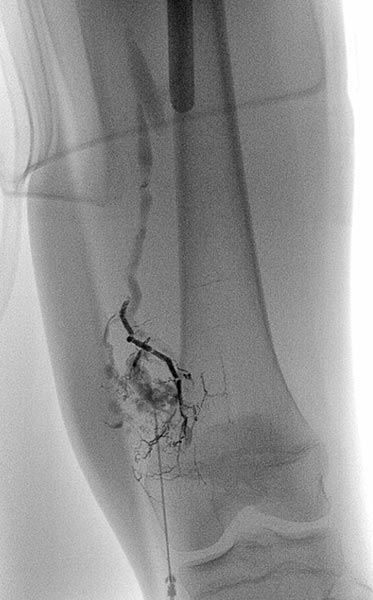

Digital subtraction angiography (DSA) in the early arterial phase shows a dilated feeding artery (so-called “feeder artery”), in this case a medial superior genicular artery. This artery is dilated over time due to chronic hyperperfusion with increased blood flow.

Digital subtraction angiography (DSA) in the arterial phase 2 s later shows some minor arteriovenous fistulas.

Digital subtraction angiography (DSA) in the interstitial and early venous phase again 4 s later shows no direct early venous outflow of the contrast agent but, instead, a pooling phenomenon. In an arteriovenous malformation, an immediate venous outflow would be seen because of multiple direct arteriovenous communications.